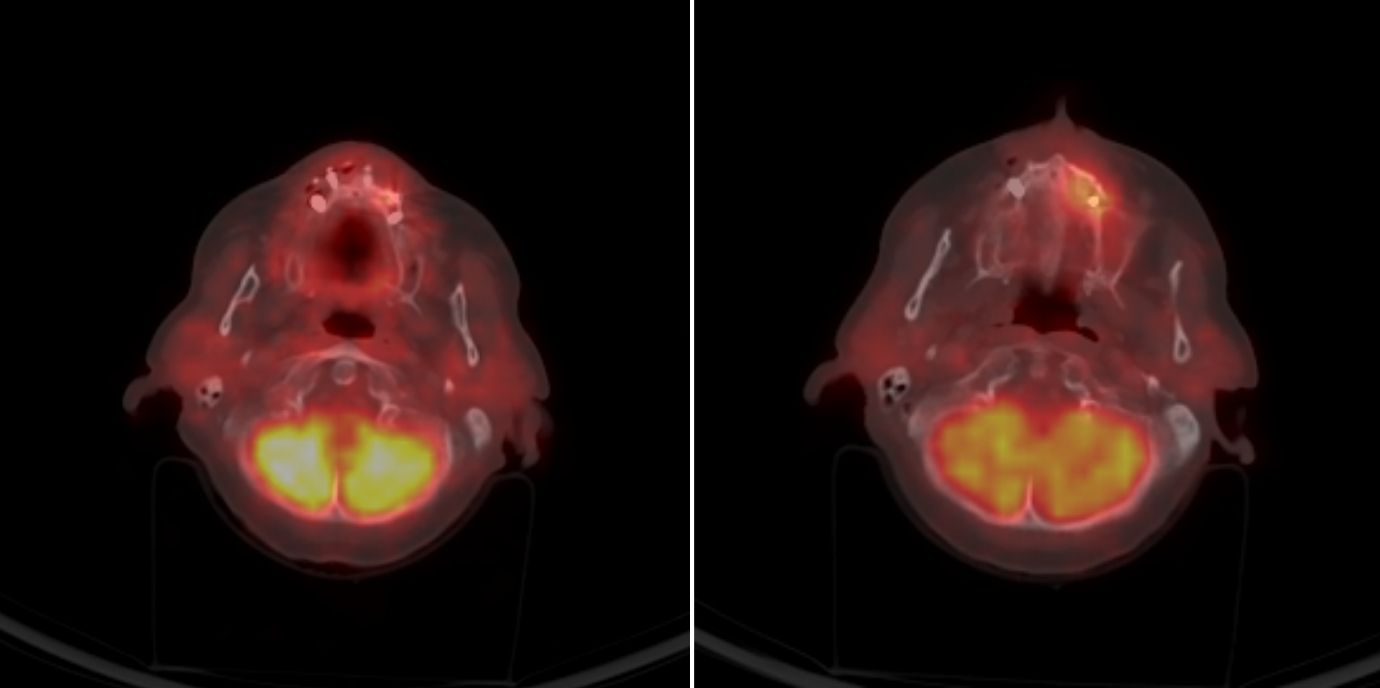

PET-CT-Bilder machen Entzündungsherde im Kiefer sichtbar. Dadurch ermöglichen sie es, frühzeitig und sehr genau vorherzusagen, wo sich unter Denosumab eine Kiefernekrose entwickeln könnte. Christine Brunner und Miriam Emmelheinz haben mit ihrem Team an der Univ.-Klinik für Gynäkologie und Geburtshilfe Patientinnen untersucht, die an Brustkrebs mit Knochenmetastasen erkrankt sind und sie haben einen Weg gefunden, wie Kiefernekrosen von vornherein verhindert werden können.

Im PET-CT leuchten Entzündungsherde am Kiefer auf. Nuklearmediziner:innen können anhand dieser Bildgebung fast bis auf den Zahn genau vorhersagen, wo sich in den kommenden durchschnittlich 238 Tagen die Kiefernekrose entwickeln wird – falls sich eine Kiefernekrose entwickelt. „Das ist wichtig“, wie Christine Brunner betont. Denn nicht jede Patientin mit einem Zahnherd, die sie im Rahmen ihrer Studie betreut hat, bekam eine Nekrose. „Aber geradezu jede, die eine Nekrose entwickelt hat, hatte vorher einen Zahnherd und zwar genau an der Stelle, an der später die Nekrose auftrat“, sagt Brunner. Die Gynäkologin ist Letztautorin, Miriam Emmelheinz firmiert als Erstautorin der Studie, die kürzlich in eClinicalMedicine (The Lancet-Gruppe) erschienen ist.

Mit einer Vorhersagezeit von im Mittel 238 Tagen und hoher Genauigkeit können Veränderungen im Kiefer lange vor der klinischen Symptomatik identifiziert werden. Dafür haben die Gynäkolog:innen von Nuklearmediziner:innen PET-CT- Bilder begutachten lassen, die vor Therapiebeginn mit Denosumab sowie alle drei Monate weiter im Verlauf aufgenommen wurden.